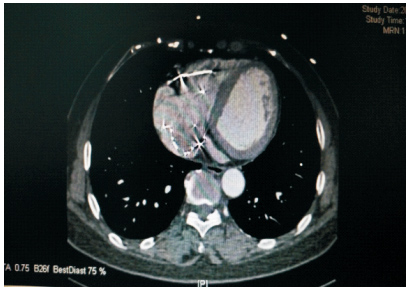

患者59岁,女性,因“发现心脏杂音3个月”于2011年1月份入院。患者2001年因下腔静脉狭窄于外院行下腔静脉支架植入术(支架厂家及型号不详),术后服用培达3个月后停药,无不适。2007年间断出现心悸及胸闷,未诊治。2011年单位体检发现心脏杂音,外院超声提示下腔静脉支架移位至右房,主动脉窦右房瘘。既往:体键。入院查体:血压120/70 mmHg(1 mmHg=0.133 kPa),心律齐,主动脉瓣第一听诊区可闻及Ⅲ/6级收缩期杂音,腹软,无压痛,双下肢不肿。入院诊断:下腔静脉狭窄,下腔静脉支架植入术后,下腔静脉支架移位,主动脉窦右房瘘。入院后相关检查:超声心动图:LV 53 mm,EF 74%,主动脉右冠窦与右房间探及破口约3~4 mm,下腔静脉入右房口处探及支架回声,支架突入右房约20 mm;胸片(图 1、2):侧位片金属支架结构影不连续,心影区偏前区可见线状高密度影。CT(图 3、4):右室游离壁、间隔壁、三尖瓣口、右房、下腔静脉近心段可见支架金属丝影。冠状动脉造影检查(图 5、6):冠状动脉未见明显异常,可见支架影随着心脏的跳动位置发生变化。